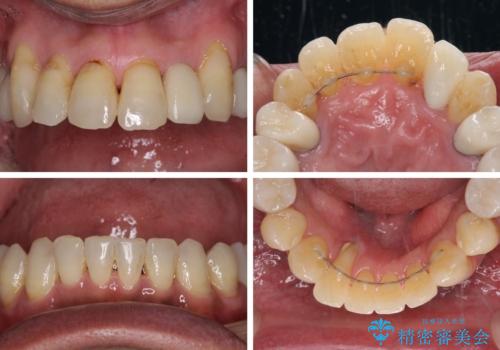

歯列不正と歯周病 総合歯科治療による全顎治療

- 前歯がのデコボコや、奥歯に咬んだときに痛みがあるとのことで来院された患者様です。

全体的に問題が多く、全てをしっかりと治療したいとのことでした。

全体的に中等度の歯周病と診断されたため、歯周外科処置やインプラントによる咬合回復から進めて行き、矯正治療による歯列改善を行った後にオールセラミッククラウンにて補綴することとしました。

初診来院時には矯正治療を行うことは想像していなかったようで、治療後には咬みやすさだけでなく、前歯が大変審美的に仕上がり、患者様には大変満足していただきました。